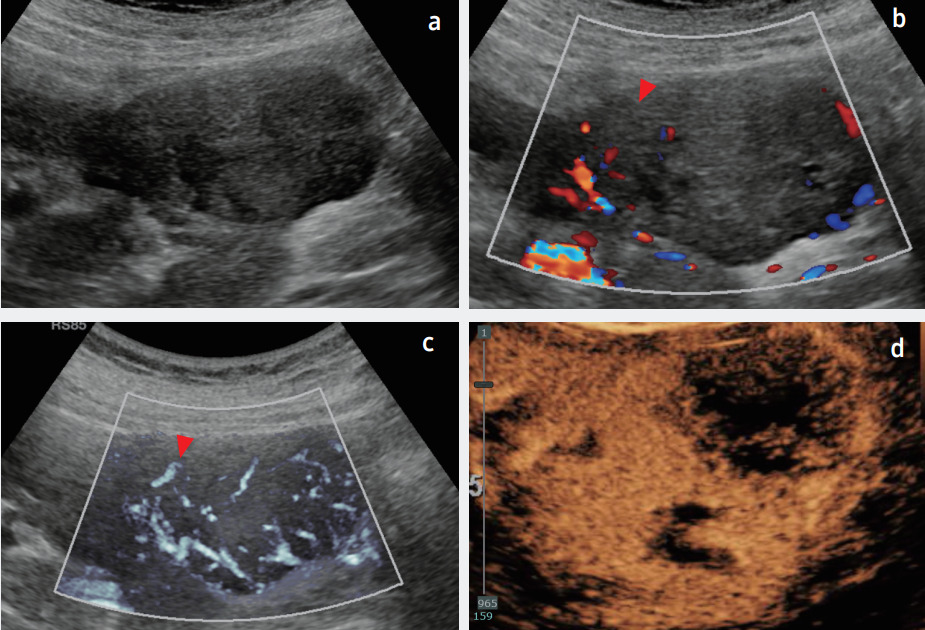

Высокая чувствительность к низкоскоростным кровотокам повышает точность диагностики. На снимке пример визуализации карциномы почки в В-режиме, цветовом допплере, MV-Flow и CEUS.

Технология MV-FlowПри выявлении очаговых поражений почек наиболее важными диагностическими вопросами, требующими решения, являются оценка характера и потенциальной клинической значимости этих поражений. При не кистозных или солидных образованиях ультразвуковое исследование помогает разделить поражения на доброкачественные и злокачественные. Кроме того, улучшенное разрешение и возможности современных допплеровских технологий, высокочувствительных к низкоскоростному потоку, таких как MV-Flow, повысили диагностический потенциал ультразвукового оборудования при диагностике образований почек даже без использования контрастов.

MV-Flow - визуализация микроциркуляции в тканях и органа, встроенное программное обеспечение ультразвуковых систем Samsung. Это усовершенствованный инструмент для определения микрососудистого кровотока, который невозможно визуализировать на обычных допплеровских изображениях. При обычной цветной допплерографии или силовой допплерографии, часто бывает трудно различить кровоток с очень низкой скоростью, поскольку он может находиться в том же диапазоне скоростей, что и фоновая ткань, в результате чего ультразвуковая система распознает низкоскоростной кровоток как шум.

Однако, MV-Flow предлагает детальное изображение низкоскоростного кровотока по отношению к окружающим тканям с высокой чувствительностью и разрешением. Он обладает более высокой способностью подавления тканевого шума, что позволяет уменьшить его. Таким образом, функция MV-Flow показывает максимально близкое изображение к контрастному методу исследования – CEUS.